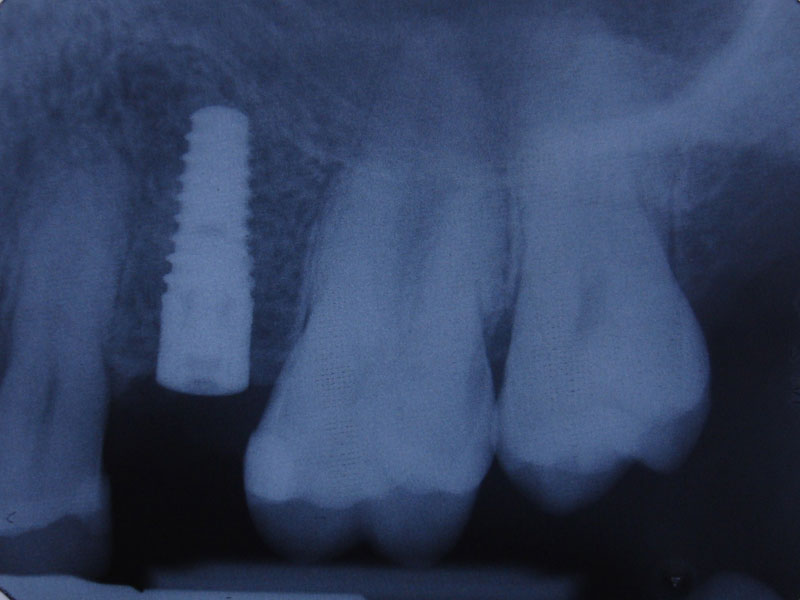

Un rol important in tratamentul cu implanturi dentare il are calitatea acestora, din ce si cum sunt fabricate. Pentru fabricarea implanturilor dentare Firma Bredent foloseste Ti de grad 4, cel mai pur titan utilizat in medicina, fara alte metale, evitand astfel riscul aparitiei complicatiilor.

De asemenea titanul este dublu laminat la rece, procedeu prin care se obtine o rezistenta mecanica superioara altor implanturi dentare care folosesc aliaje ale titanului (grad 1, 2, 3, 5 etc). In timpul procesului de fabricatie o atentie deosebita este acordata indepartarii reziduurilor de orice fel (uleiuri, acizi, substante folosite in producerea oricarui tip de implant dentar). Toate elementele utilizate ulterior in tratamentul protetic pe implanturi dentare sunt de asemenea fabricate din titan de grad 4. Prin toate acestea, numarul esecurilor este redus la minim.

Bredent produce aceste implanturi dentare in Germania, respectand standardele de calitate din Germania.